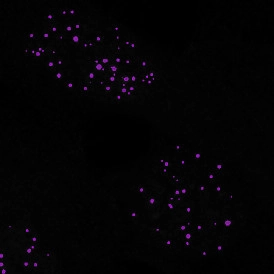

The IF Dots App provides dot detection per cell within the cell compartments for up to four markers in a sample (e.g., FISH, RNA, oil droplets). Each segmented cell compartment is measured for up to 20 intensity, statistic, and morphometric parameters. Dot measurement parameters are provided per cell compartment (e.g., nucleus, cytoplasm) and per dot and include count, mean intensity, total dot area, the sum of intensity.

App Category 2